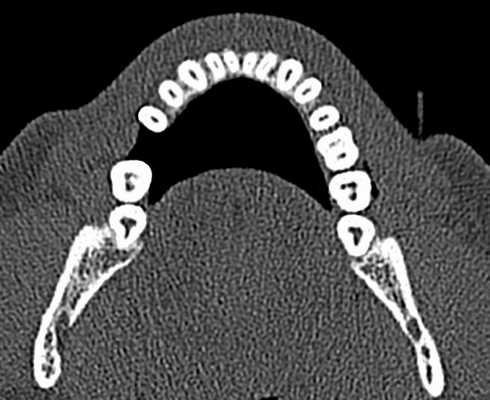

В исследование были включены 25 пациентов с диагнозом локальной рецессии, с клинической картиной, при которой отмечалась рецессия только у одного из идентичных зубов (рис. 1). Рис. 1. Исследование проводили у каждого пациента в области идентичных зубов. В данном случае: зуб 1.3 с рецессией, 2.3 — без рецессии. Исследовали 30 зубов, имеющих рецессию от 1,0 до 4,8 мм. Контрольная группа включала в себя 30 идентичных зубов с противоположной стороны, не имеющих рецессии (6 зубов имели минимальную потерю прикрепления — до 0,5 мм). Возраст пациентов составлял от 21 года до 36 лет, среди них было 13 женщин и 12 мужчин.

КЛКТ проводили на конусно-лучевом компьютерном томографе J. Morita Accuitomo 170, поле сканирования (FOV — field of view) — 8×8 см, угол ротации — 360, размер воксела (Voxel) — 0,16 мм.

С целью улучшения визуализации анатомических образований на компьютерном томографе при проведении сканирования применяли внутриротовой ретрактор соответствующего размера. Таким образом, отодвигая мягкие ткани губ и щек, исключали наслаивание теней и получали точную визуализацию анатомических образований пародонта.

Перед оценкой данных проводили настройку коррекции яркости и контрастности для максимальной визуализации вестибулярной костной пластинки, а также центрирование осей координат по вертикальной оси зуба для стандартизации прохождения среза.

Для повышения точности исследования проводили 3 вестибуло-оральных реформата относительно центральной оси с шагом 0,5 мм.